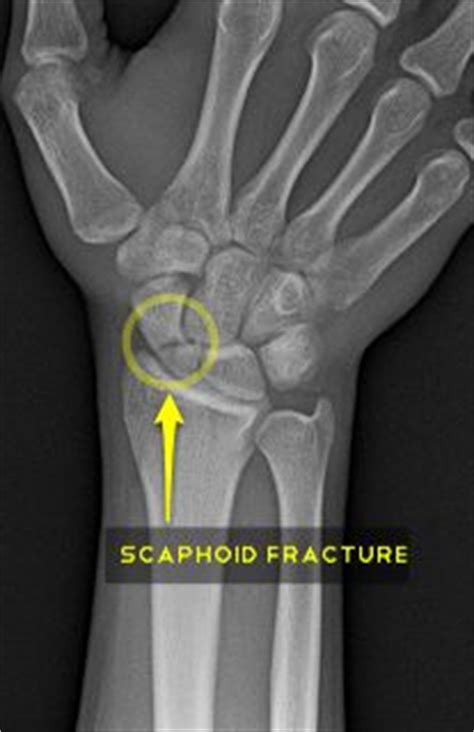

Scaphoid (Wrist Bone) Fracture - Orthopedic Specialists of ...

Scaphoid (Wrist Bone) Fracture - Orthopedic Specialists of ... from orthopedicspecialistsofseattle.com